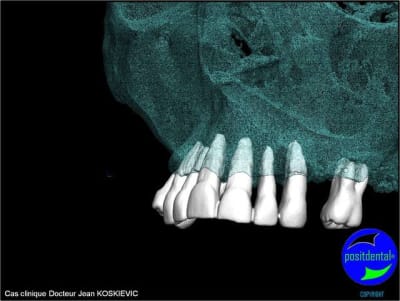

rendu 3D maxillaire sup, pano et photo

3D maxillaire inférieur et photo

et la projet 10 implants maxillaire sup